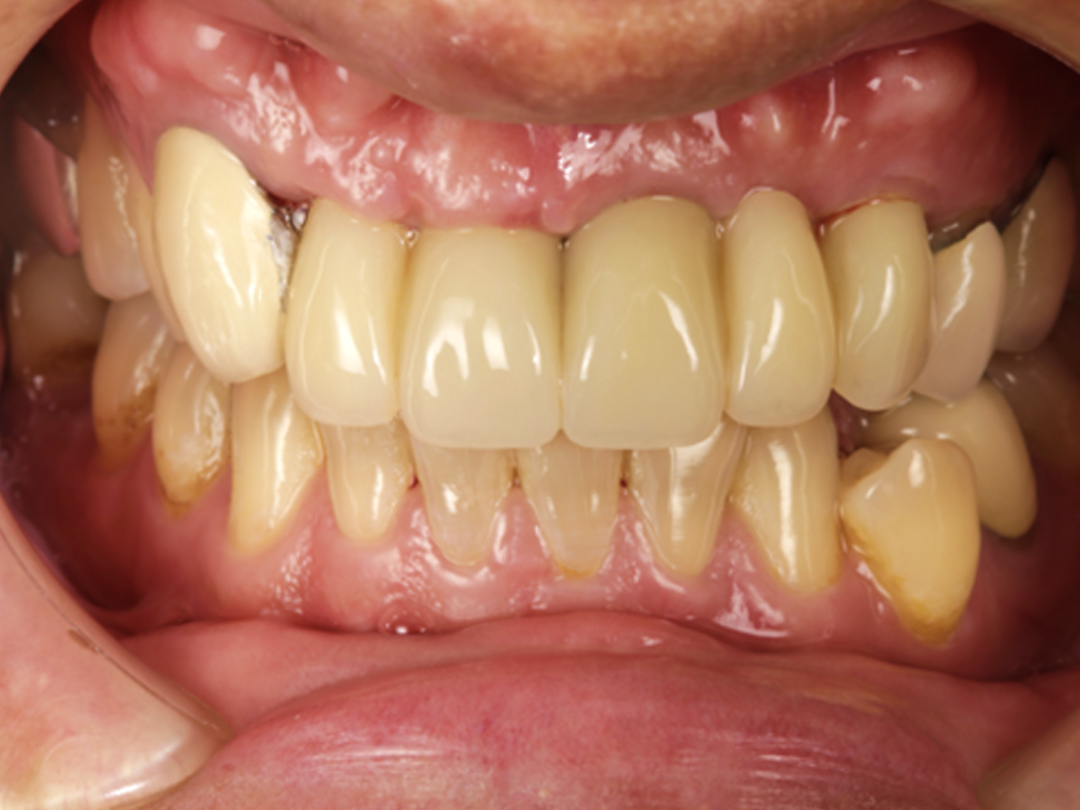

術後  假牙安裝

雖然只有三顆植牙、五顆假牙,完成後廖先生瞬間從大叔變歐巴。『原來我這麼帥』,辛苦經過一連串的治療,還給廖先生一個自信的微笑。